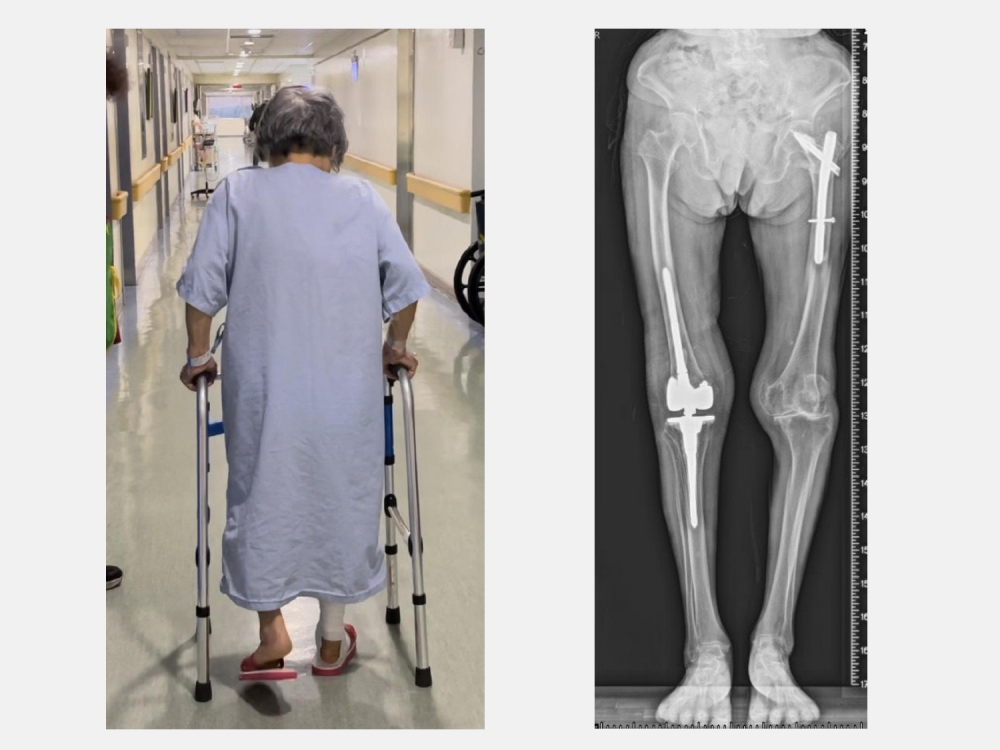

黃部長回憶門診當天的情形,老太太一臉沮喪由家屬推著輪椅來到門診,X光一看是人工膝關節旁的粉碎性骨折,由於年紀大骨質疏鬆嚴重,人工關節就像地基出現天坑一樣也整個鬆動。當天剛好是她的生日,痛苦了一個星期,生日願望只希望在餘生還能再站起來走路。

由於老太太的骨質疏鬆嚴重,不僅是粉碎性骨折也連帶傷到膝關節的韌帶。黃部長使用新式預鎖式樞紐設計的人工關節,可以取代韌帶的功能也可填充骨頭缺損來重建一個穩定的膝關節。

老太太手術當天下午就可以自己拿著助行器下床上廁所。此外,從手術隔天開始,除了骨質疏鬆症的治療,還搭配手術後疼痛中醫輔助醫療,復健科醫師也根據老太太的需求安排復健運動,在病床邊開始固定式腳踏車訓練。在手術後第5天,老太太開心的出院走路回家。